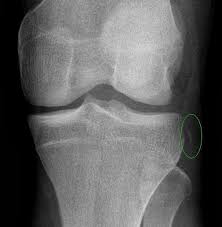

Zamanla, özellikle yaşlanma ve tekrarlayan mekanik stresle, kıkırdak yapısı bozulabilir — bu durum osteoartrit gibi hastalıkların temelini oluşturur.